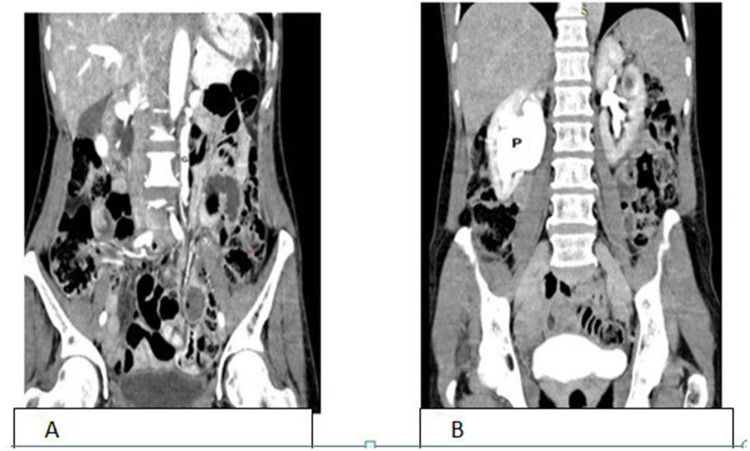

我们报告了一例罕见的左侧胡桃钳综合征和右侧输尿管盆腔交界处梗阻(UPJO)并发症,该患者为成年女性,在出现间歇性双侧侧腹疼痛后经 CT 尿路造影确诊。为此,我们为她实施了安德森-海因斯肾盂成形术(Anderson-Hynes pyeloplasty)以治疗右输尿管盆腔梗阻,最初是在腹腔镜下进行的,但由于支架植入困难而改为开腹手术。她术后恢复顺利,术后第三天就出院了。胡桃钳综合征的症状对患者来说并不严重,因此我们计划对她进行保守治疗。

We report rare case of concomitant left nutcracker syndrome and right ureteropelvic junction obstruction (UPJO) on adult female patient diagnosed by CT urogram after she presented with intermittent bilateral flank pain. For this we did Anderson-Hynes pyeloplasty for right ureteropelvic obstruction, it was laparoscopic initially but due to difficulty of stenting it is changed to open. She had smooth post-op course then discharged on 3rd post-op day. Symptoms of nutcracker syndrome are not that much bothersome for the patient so we planned to follow her conservatively.